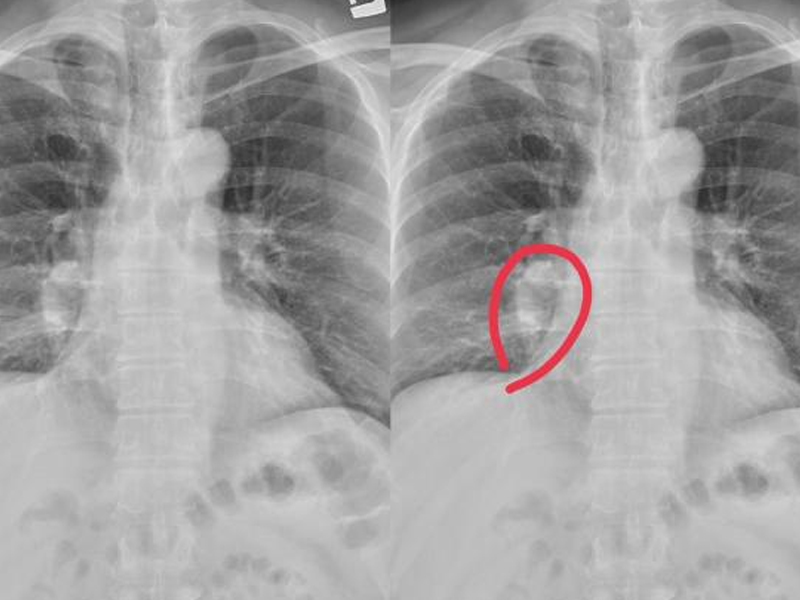

腦幹出血是神經系統的重症,疾病死亡率高。腦幹出血量在 15ml 以下,死亡率約 17.1% 左右;出血量高於 15ml 以上,死亡率 81.8% 左右;若超過20ml死亡率更高。

高血壓動脈硬化是腦幹出血的主要病因,腦幹出血是因高血壓導致基底動脈中央之破裂引起。在數秒到數分鐘內患者就會昏迷、四肢癱、針尖般瞳孔,數小時內會死亡。

1. 腦出血:實質腦內的血管破裂出血。

2. 丘腦出血:破入腦室後容易發生梗塞性腦積水。

3. 橋腦出血:約佔腦出血的10%,多因基底動脈的腦橋支破裂導致。

4. 小腦出血:只實質小腦內的出血,與高血壓直接相關。